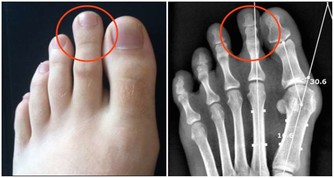

1、延緩骨骼老化

一個人衰老,骨骼會率先顯現脆弱的一面,延緩骨骼衰老對促進年輕很有幫助。相比跑步,太極的活動量並不大,在這輕緩的動作裡,能改善血液循環,對提高骨骼的物質代謝也有幫助,鈣、磷沉澱在骨骼裡,會增強骨骼的密度、彈性,進而可以預防骨質疏鬆的發生,不斷的延緩衰老。